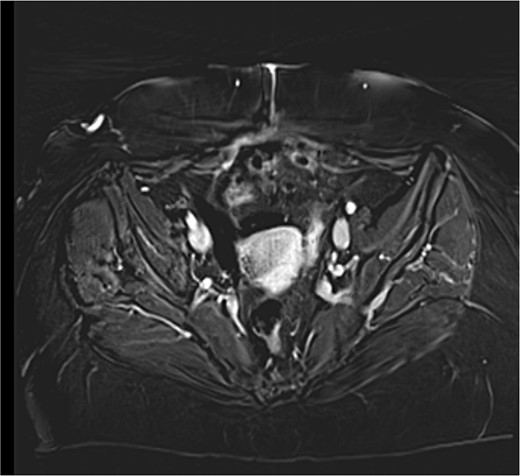

A close follow up was decided at the MTD meeting. Every 3 months a follow up MRI abdomen and CT thorax was performed in order to exclude recurrence. The patient is well and without evidence of recurrence 6 months after surgery (Fig. 3).

MRI T1 axial 3 months postoperative with no residual mass detected.